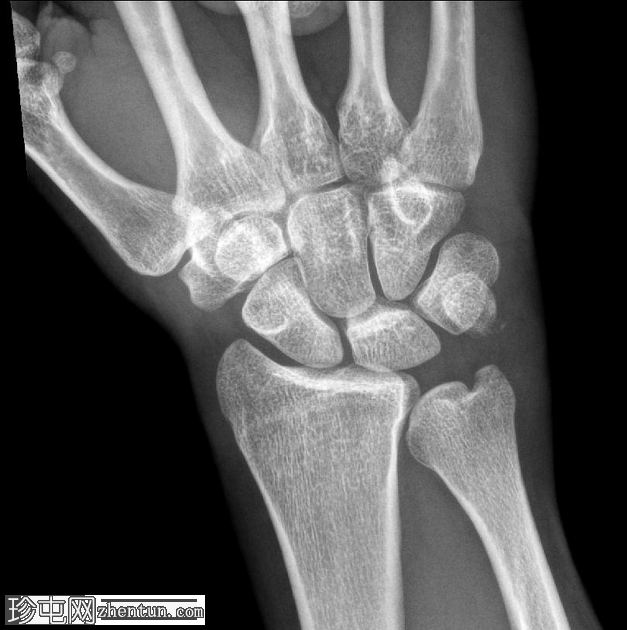

正位片

可见豌豆骨皮质明显中断,并伴有一小块邻近骨碎片,符合皮质骨折的表现。此外,其上方软组织肿胀,提示急性骨折。

尺骨茎突可见透亮区,符合无移位尺骨茎突骨折的表现。